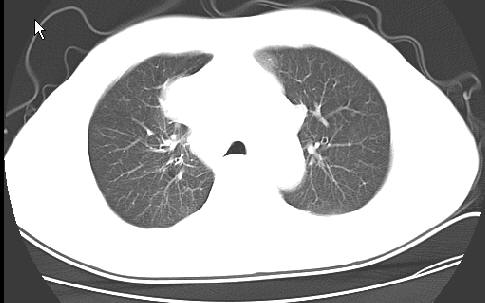

以下是引用ct诊断高手在2009-5-2 19:08:00的发言:[br]我考虑右侧中央型肺癌 伴右肺节段性不张,两肺及纵隔淋巴结转移,右侧胸腔积液。

以下是引用zjzjr在2009-5-2 20:16:00的发言:[br]肺结核,转移瘤.纵隔淋巴结转移或淋巴瘤,右侧包裹性积液、斜裂积液。心包积液。